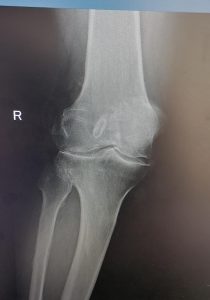

KNEE REPLACEMENT

As the knee ages it may come to a point where cartilage has eroded away to expose bone. Bone grinding on bone as a person is walking is very painful. Fortunately orthopaedic science has evolved to a solution whereby the knee can be replaced with a mechanical prosthesis.

Presently, the results are generally very good with excellent pain relief and mobility after the operation. Longevity of the prosthesis has improved to a point where the 10 year survival is more than 95% in some series.

As all surgery, the procedure is not entirely risk free. Deep venous thrombosis at 1% incidence and infection at 0.4% are most common complications, but stiffness, bleeding, nerve injury etc. can occur.

Below see the pre operative pictures of a normal knee, a diseased knee and a replaced knee.